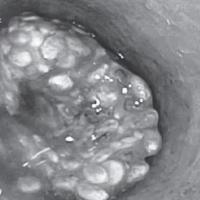

Pri operaciji promene pola, koju je ispratilo i vađenje materice, lekari su otkrili da je Marko trudan.

Osoba, koja je uzela muško ime Marko, bila je u poodmakloj fazi procesa promene pola nakon uklanjanja grudi. Trebalo je da uradi histerektomiju radi uklanjanja materice, a onda su lekari u bolnici u Rimu otkrili trudnoću.

Veruje se da je ovo prvi slučaj te vrste u Italiji, iznenađujuće otkriće izazvalo je zabrinutost za zdravlje bebe i da li je na fetus uticala procedura kojima je Marko do sada bio podvrgnut.